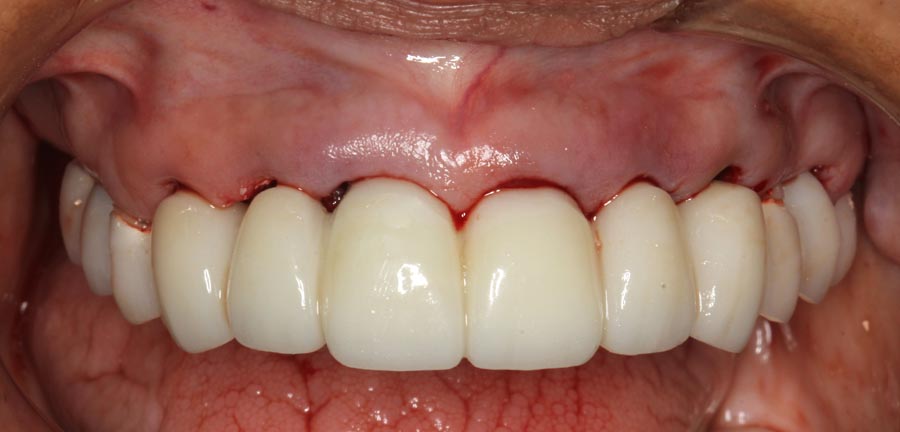

Smile GalleryImplant RestorationsFull Mouth Implant Restoration Full arch zirconia implant bridge (full smile) 1 of 37 Pre-op full smile Pre-op lips retracted Pre-op panoramic x-ray Extraction of strategic teeth Placement of implants Extraction of some remaining teeth after verification of adequate implant stability Occlusal view Post-op panoramic x-ray Immediately fabricated provisional restoration (tissue side view) Immediately fabricated provisional restoration (occlusal side view) Immediate provisional delivered on day of surgery Immediate provisional 2 weeks later Scalloped tissue developed from the provisional at 2 weeks Jig used for making a master impression Provisional in place (full smile) Provisional in place (lips retracted) Provisional in place (right side) Provisional in place (left side) Wax try-in (full smile) Wax try-in (right side full smile) Wax try-in (left side full smile) Wax try-in (full face, lips together) Wax try-in (full smile) Wax try-in (right side) Wax try-in (left side) Wax try-in (lips retracted) Full arch zirconia implant bridge on master cast (frontal view) Full arch zirconia implant bridge on master cast (occlusal view) Implant positions and soft tissue representation on master cast (occlusal view) Soft tissue representation on master cast (frontal view) Full arch zirconia implant bridge (tissue side view) Soft tissues on day of delivery (occlusal view) Soft tissues on day of delivery (frontal view) Full arch zirconia implant bridge delivered (lips retracted) Full arch zirconia implant bridge (lips retracted, close up) Post treatment panoramic x-ray Full arch zirconia implant bridge (full smile)